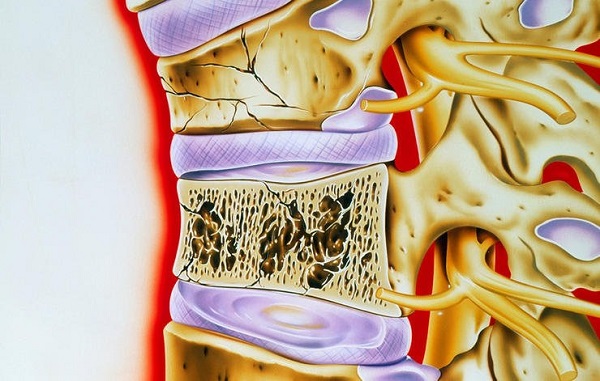

اگر به تازگی تصادفی داشته اید، داروهای خوراکی استروئیدی مصرف می کنید (که می تواند استخوان ها را تضعیف کند)، یا پوکی استخوان در شما تشخیص داده شده است، هر گونه کمر درد باید جدی گرفته شده و به پزشک مراجعه کنید. شما ممکن است شکستگی ستون فقرات داشته باشید که می تواند به کاهش قد، وضع اندامی خمیده و حتی مشکلات تنفسی و گوارشی منجر شود.